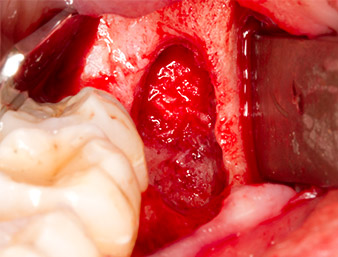

To expose the root remnant with as little trauma as possible to the tissue, a further instrument was used (Piezomed S2) that is primarily indicated for preparing the lateral window in augmentations of the sinus floor. The diamond-coated ball was additionally used to smooth sharp bone edges (Fig. 6 and 7). All the Piezomed attachments were used with the relevant automatic default setting without booster function.

Using an instrument for periodontal debridement (Piezomed P1), the periodontal ligament space of the radix relicta was then widened minimally (Fig. 8).

The same activated instrument was inserted into the root canal and loosened the fragment as a result of its micro-oscillating vibrations (Fig. 9, 10).

It was then possible to remove the approximately six-millimetre-long root remnant in one piece with the P1 attachment (Fig. 11).

Periapical inflamed tissue was also removed very carefully with a manual excavator. Fig. 12 shows the empty alveole with exposed inferior alveolar nerve.